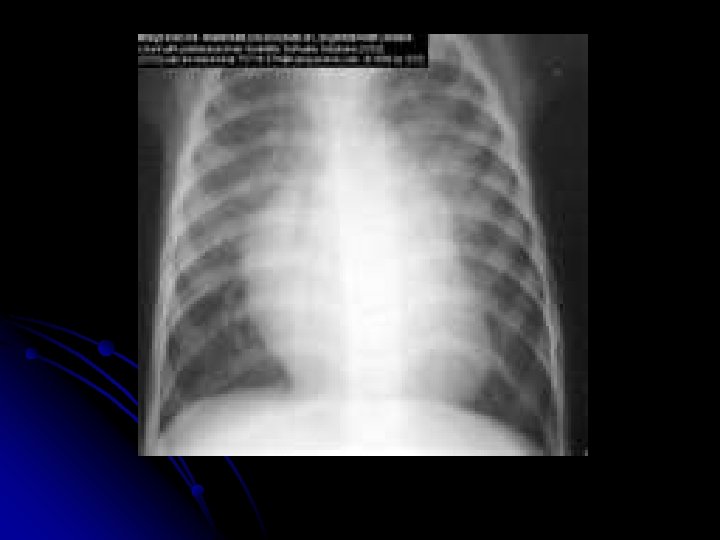

The Diagnostic testing used to evaluate the presence & severity of Mitral Stenosis includes: ECG Chest Radiograph 2 D Echocardiogram Doppler Study Trans. Esophageal Echocardiography

COMPLICATIONS OF MITRAL STENOSIS ATRIAL FIBRILLATION LUNG CONGESTION BLOOD CLOTS with SYSTEMIC EMBOLIZATION PULMOARY HYPERTENSION CONGESTIVE HEART FAILURE